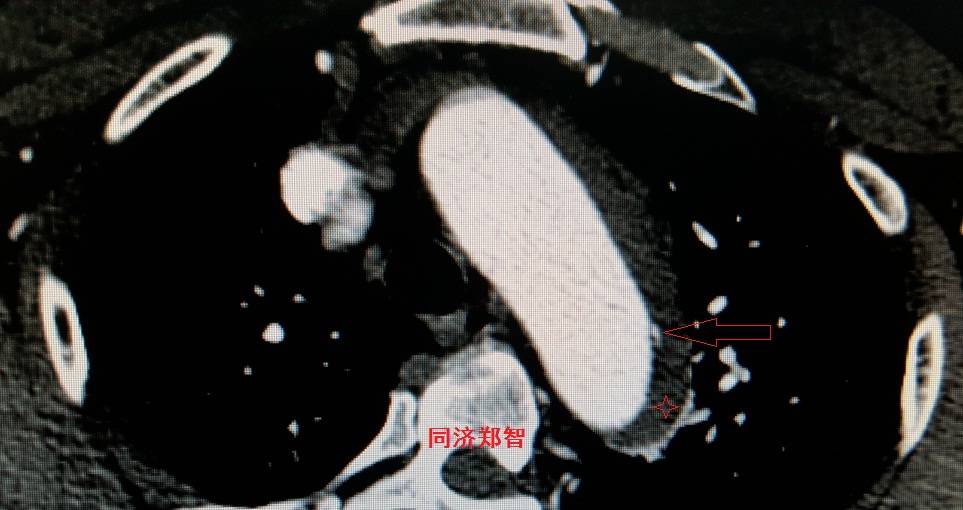

病例十

腹主动脉平扫CT提示正常外周一圈的钙化影中有内移的钙化影(红色箭头所示),CTA 证实为腹主动脉夹层